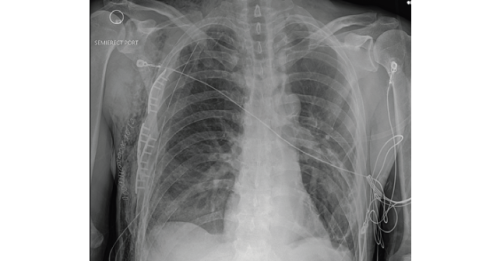

Case A 58-year-old male with a history of alcohol abuse presented to the emergency department (ED) as…